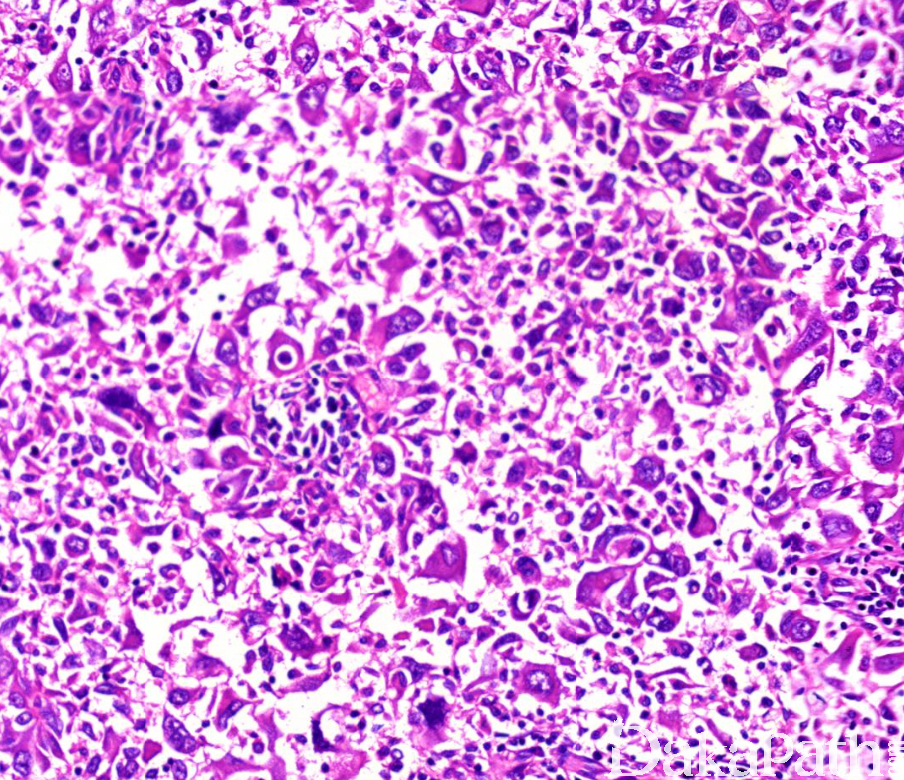

是一种分化差的非小细胞肺癌,至少 10%的区域由梭形细胞和/或巨细胞构成,或者完全由梭形和巨细胞成分组成。

在腺癌、鳞状细胞癌或未分化非小细胞癌的背景上至少存在 10%的密切相关的恶性梭形细胞和/或巨细胞成分;

部分病例可完全由梭形细胞和巨细胞组成,分别称为梭形细胞癌和巨细胞癌;

梭形细胞形态不一,可从上皮样到具有平滑肌特点的间充质样细胞均可见到,可呈束状或席纹状排列;

巨细胞黏附性差,呈多角形,胞浆致密,嗜酸性,核多形性,可单核、多核或多叶核;

常见到大血管浸润及广泛坏死;